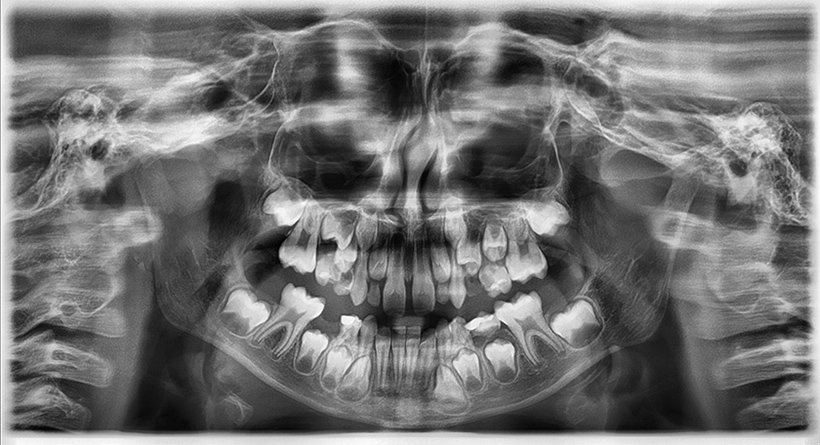

Radiografia digitală panoramică sau Ortopantomografia este radiografia digitală care ne oferă o imagine de ansamblu la toţi dinţii din cavitatea bucală, inclusiv sinusurile maxilare şi aticulaţiile temporo-mandibulare. Este indicată la începerea unui tratament stomatologic pentru a vedea zonele mai greu accesibile ale dinţilori, retracţiile osoase, existenţa şi adâncimea pungilor parodontale, existenţa dinţilor incluşi, etc.